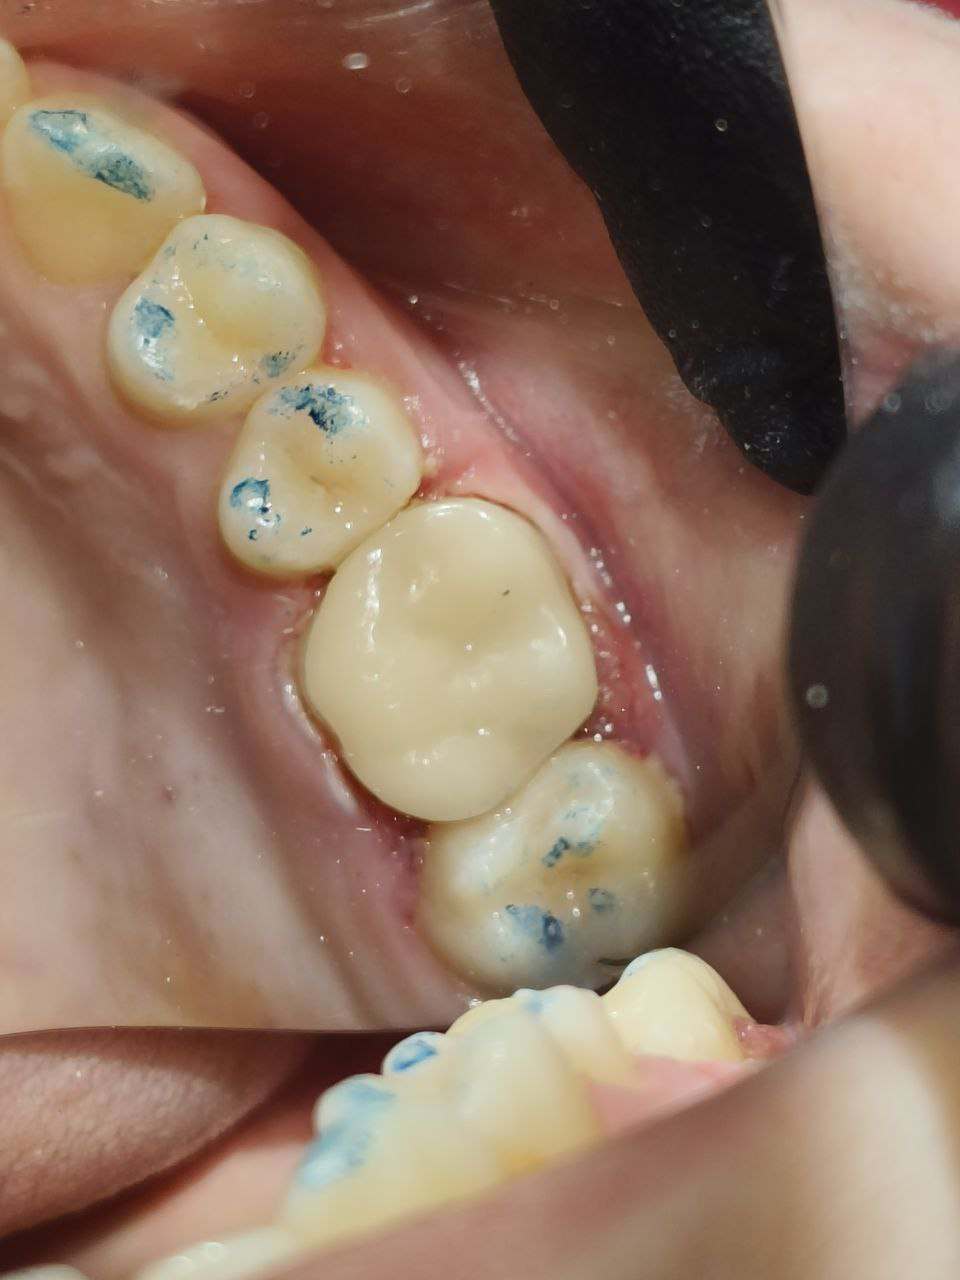

На фотографиях видно как кариес "испортил" всю жевательную поверхность зуба, в таком случае должен полностью убрать кариозные ткани, предварительно окрасив их специальным раствором кариес индикатором. Затем ткани "потярянные" изза кариеса замещаются накладкой.